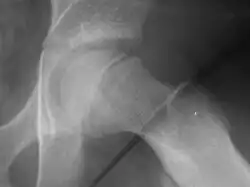

| Radiogram of slipped capital femoral epiphysis |

Klein's line or the line of Klein is a virtual line that can be drawn on an X-ray of an adolescent's hip parallel to the anatomically upper edge of the femoral neck. It was the first tool to aid in the early diagnosis of a slipped capital femoral epiphysis (SCFE), which if treated late or left untreated leads to crippling arthritis, leg length discrepancy and lost range of motion. It is named after the American orthopedic surgeon Armin Klein at Harvard University, who published its description and usefulness in 1952. Subsequent modification of its use has increased the sensitivity and reliability of the tool.

Klein's line is a virtual line that can be drawn on an X-ray of a child's hip parallel to the upper edge of the femoral neck. If the line does not intersect with the outermost part of the femoral head 's ball-like end, the diagnosis of a slipped capital femoral epiphysis (SCFE) is confirmed.[1]